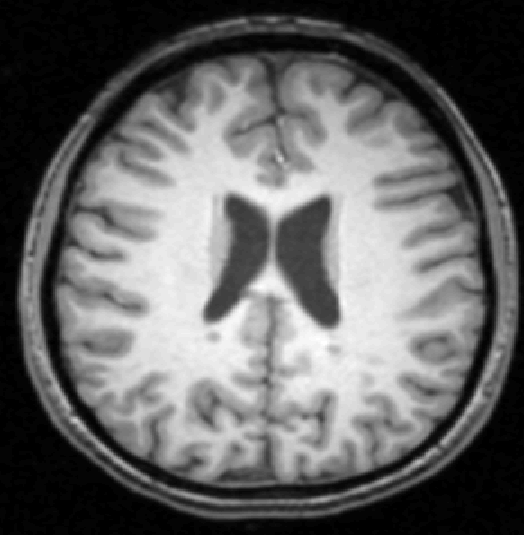

We use images from three different studies (see Fig. 1 for examples of slices):

10 MS patients from the MS Lesion Challenge [11] scanned at the Children’s Hospital of Boston (CHB), scanned with T1, T2 and FLAIR at 0.50.50.5mm resolution.

2.

- 3.

Here again the differences between study populations influence the class priors. On average, the percentage of voxels that are lesions are 1.6%, 2.6% and 0.2% in CHB, RSS and UNC respectively. The differences between subjects also vary: these are relatively small for CHB and UNC, but very large for RSS. In RSS, the subject with the least lesion voxels has only 0.08%, while the patient with the most lesion voxels has 14.3%.